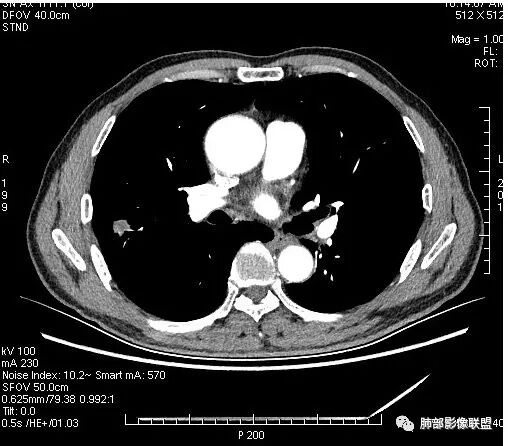

影像学改变:

4.病灶轻到中度强化。病灶内血管走行较完好,病灶旁血管局部显示粗大。

5.支气管关系不确定。